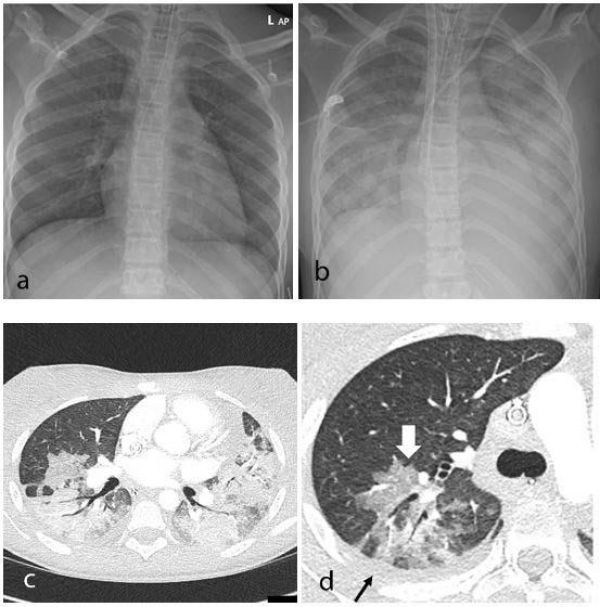

Image: Thoracic findings in a 15-year-old girl with Multisystem Inflammatory Syndrome in Children (MIS-C). (a) Chest radiograph on admission shows mild perihilar bronchial wall cuffing. (b) Chest radiograph on the third day of admission demonstrates extensive airspace opacification with a mid and lower zone predominance. (c, d) Contrast-enhanced axial CT chest of the thorax at day 3 shows areas of ground-glass opacification (GGO) and dense airspace consolidation with air bronchograms. (c) This conformed to a mosaic pattern with a bronchocentric distribution to the GGO (white arrow, d) involving both central and peripheral lung parenchyma with pleural effusions (black small arrow, d). (Credit: Radiological Society of North America)